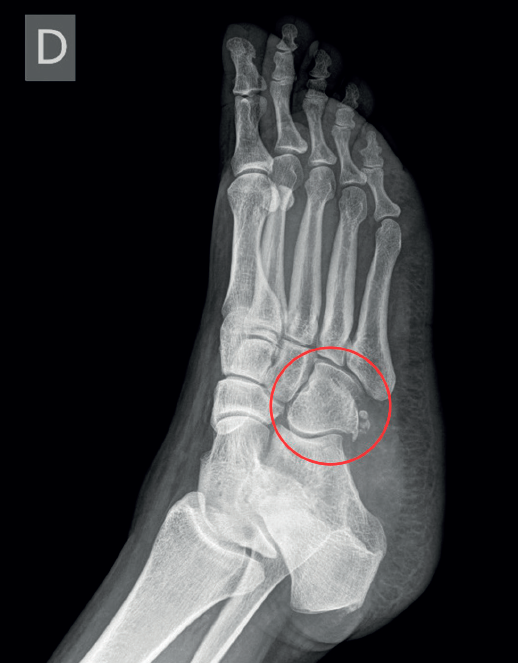

Se realizaron radiografías bilaterales del pie que evidenciaron la presencia de OP bilateral, con irregularidad en el margen del OP derecho. Inicialmente, se sospechó fractura del hueso cuboides (Figura 1); sin embargo, una tomografía computarizada (TC) descartó dicha fractura e identificó un trazo de fractura en el OP derecho, sin desplazamiento (Figura 2). Se realizó resonancia magnética (RM) del pie derecho que confirmó edema en OP del TPL, no desplazada ni complicada. TPL íntegro.

El diagnóstico diferencial incluyó esguince de tobillo de grado I, fractura del hueso cuboides, lesión del TPL y fractura de la base del quinto metatarsiano. Finalmente, el diagnóstico definitivo fue fractura del OP derecho, entidad poco frecuente como causa de dolor lateral del pie.